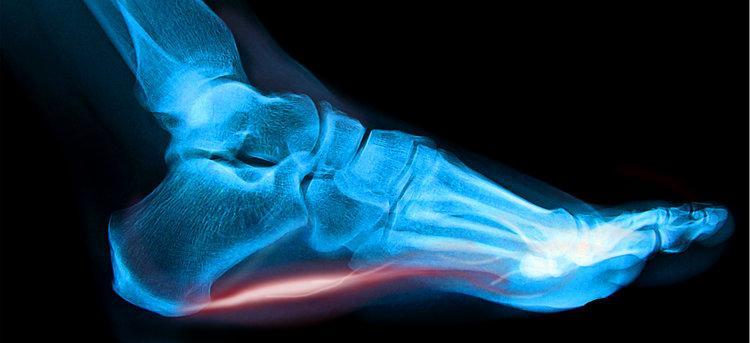

- Achilles Tendinopathy

- Plantar Fasciitis